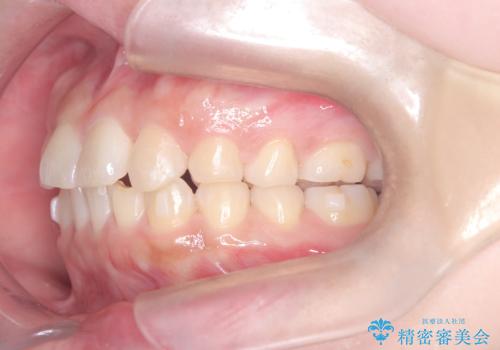

- 「歯の捻じれとがたつき」を主訴に来院された患者様です。

軽度な捻転と叢生だったため、インビザラインのモデレートで治療を行いわずか半年で治療を終える事が出来ました!

目立たないマウスピース矯正【インビザライン】を使用し、

わずか6ヵ月で歯並びがキレイに整いました!